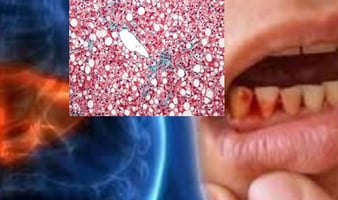

مرض الكبد الدهني، المعروف أيضًا باسم مرض الكبد الدهني غير الكحولي (NAFLD)، يتضمن تراكم الدهون الزائدة في الكبد.

تشمل التغيرات الجلدية المرتبطة بمرض الكبد الدهني اليرقان، وحكة الجلد، والتهاب الجلد، والوردية، والأوردة العنكبوتية، واعتلال الجلد الأسود. يمكن أن تتنوع البقع الجديدة المسطحة أو المرتفعة على الجلد من التبييض إلى الاحمرار.

يمكن أن يظهر مرض الكبد الدهني أيضًا أعراضًا على الوجه، مثل اليرقان، والوردية، والتهاب الجلد، وحكة الجلد، والأوردة العنكبوتية، واسمرار الجلد.

هناك نوعان رئيسيان من الكبد الدهني: مرض الكبد الدهني غير الكحولي (NAFLD) الذي يتضمن تراكم الدهون في الكبد، ومرض التهاب الكبد الدهني غير الكحولي (NASH) الذي يترافق مع علامات الالتهاب وتلف خلايا الكبد.

التهاب الكبد: يبدأ من حالة دهون إلى حالة ملتهبة (متورمة).

التليف: يتكون نسيج ندبي نتيجة الالتهاب الذي يؤدي إلى تلف الكبد.

تليف الكبد: حيث يتم استبدال الأنسجة السليمة بنسيج ندبي.